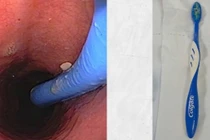

nuot-ban-chai1.jpg

Bàn chải đánh răng trên phim chụp - Ảnh BVCC

nuot-ban-chai.jpg

Ê-kíp phẫu thuật cho bệnh nhân - Ảnh BVCC

Trực tiếp thực hiện thủ thuật là BS Trần Mạnh Hùng, Phó Trưởng khoa Chẩn đoán hình ảnh cho biết, quá trình can thiệp gặp nhiều khó khăn do bàn chải có kích thước 15 x 2 cm, nằm ngang ở thân vị dạ dày;

Dị vật dài, trơn trượt, gây khó cho việc đưa dụng cụ tiếp cận và gắp đúng đầu bàn chải; Nguy cơ dị vật cọ xát, làm tổn thương tâm vị và thực quản khi kéo ra ngoài.

nuot-ban-chai-3.jpg

Bàn chải đánh răng trên nội soi - Ảnh BVCC